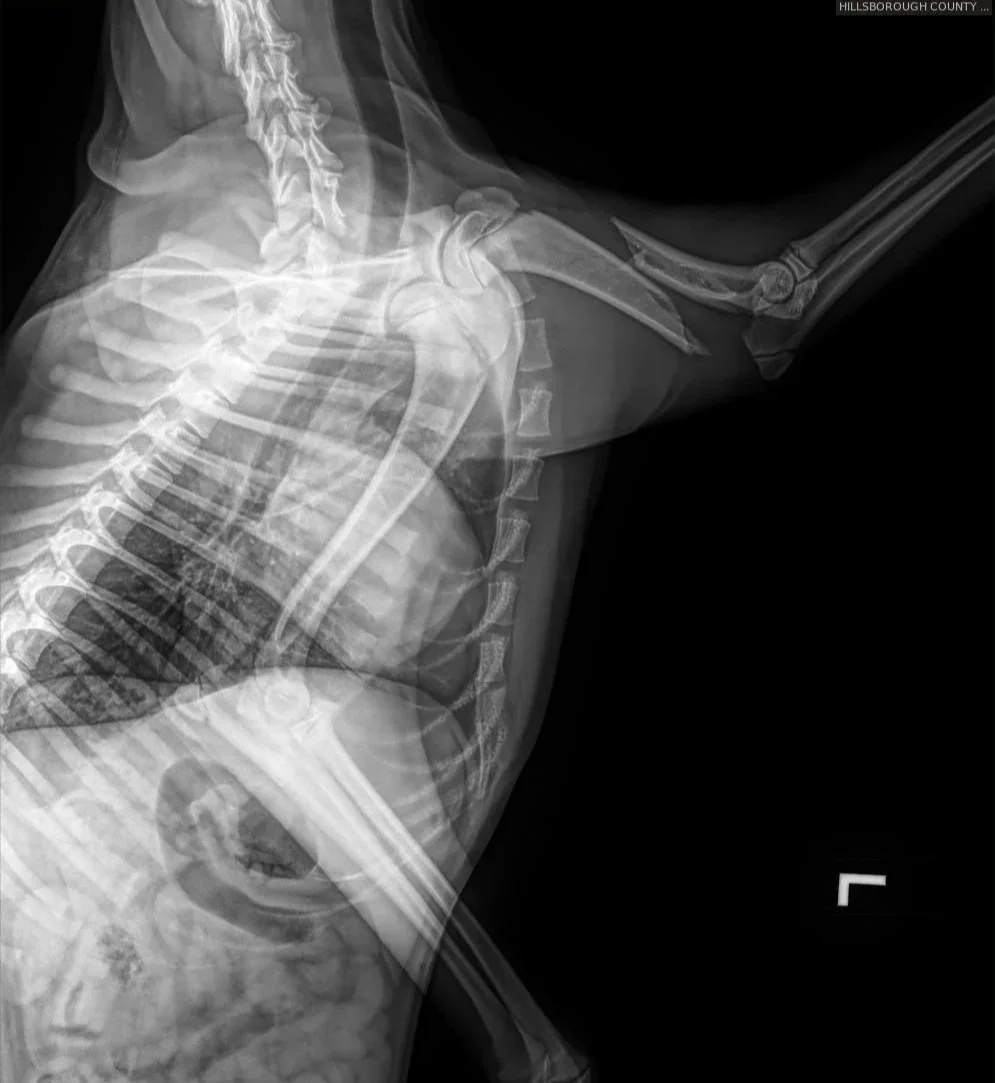

Goldie is a young and sweet girl who deserves a chance at fixing her leg and getting adopted into a forever home. We greatly appreciate any and all help. She was found after being hit by a car and was lucky to be discovered by kind people who rushed her in for care. The shelter team did an incredible job stabilizing her and keeping her comfortable, but she needed more specialized treatment.

UPDATE: Goldie was able to get the surgery she desperately needed for her injured leg. Goldie did amazing in surgery and is recovering like a champ. 💛 She came into the shelter after reportedly being hit by a car, but after multiple vets — including her orthopedic surgeon — looked her over, they all agreed her injury was probably older than that. Her body had already started forming muscle contracture trying to deal with a complete humerus fracture. This poor girl has definitely been hurting for a bit.